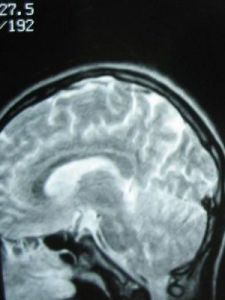

如懷疑糖尿病者需進行血糖、尿糖測定;心血管疾病需進行心電圖、超聲心動圖甚至心血管造影檢查,必要時也可進行血常規、血電解質、肌鈣蛋白、24小時動態心電圖測定、有創性電生理檢查、直立傾斜試驗、經食管超聲心動圖等檢查;內分泌疾病的診斷需有垂體、腎上腺或甲狀腺功能測定的證據。如懷疑肺栓塞,可進行血氣分析、肺動脈CT、肺通氣灌注掃描等。如懷疑顱內病變或局灶性神經病變,則要進行腦電圖、頭顱和腦CT及磁共振。